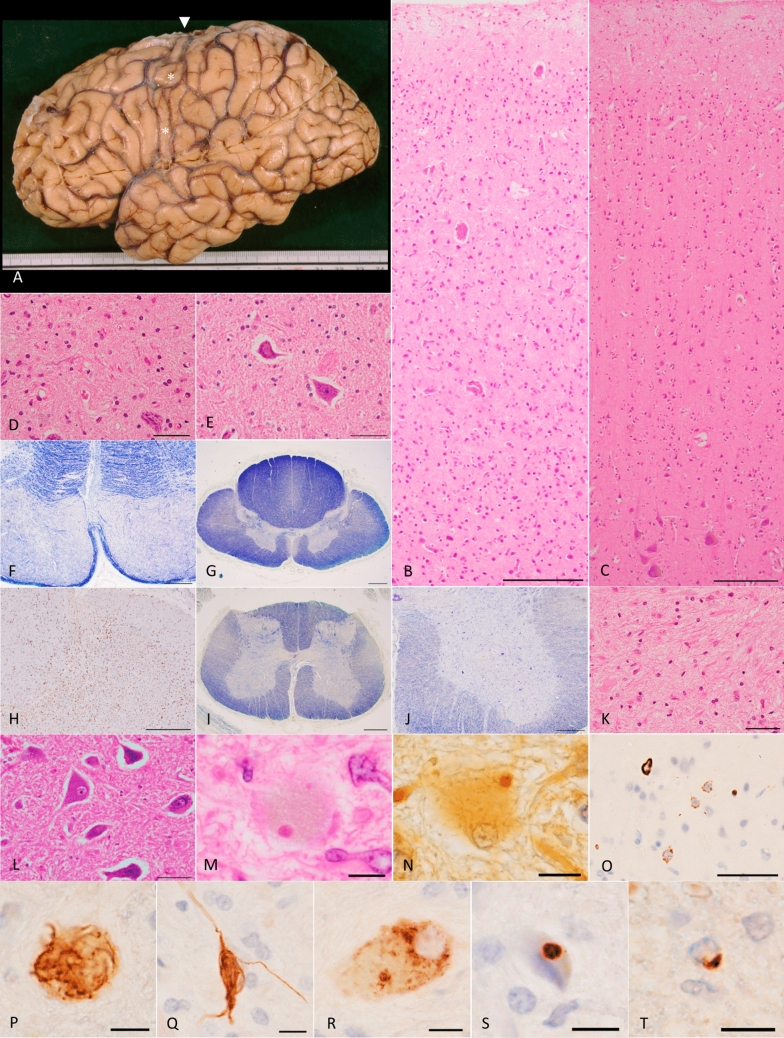

Phosphorylated TDP-43 pathology, Bunina bodies, and severe loss of the upper and lower motor neurons in the older brother (IV-1) with a homozygous c.518dupC frameshift variant in DNAJC7.a Lateral view of the left hemisphere, showing severe atrophy in the precentral gyrus (asterisks). Arrowhead indicates the top of the precentral gyrus, the width of which is extremely thin. b Severe neuronal loss with gliosis in all cortical layers of the primary motor cortex. Betz cells are nearly completely absent. H&E stain. Scale bar: 200 μm. c Primary motor cortex in a 68-year-old pathologically normal control case. Betz cells are present in layer V, and the structure of the cerebral cortex is spared. H&E stain. Scale bar: 200 μm. d Severe neuronal loss with gliosis in the hypoglossal nucleus. A remaining neuron shows shrinkage of the cell body. H&E stain. Scale bar: 50 μm. e Hypoglossal nucleus in a 51-year-old pathologically normal control case. Neither glial proliferation nor shrinkage of neurons is observed. H&E stain. Scale bar: 50 μm. f Severe degeneration in the pyramidal tract within the medulla oblongata, as visualized by Klüver–Barrera stain. Scale bar: 500 μm. g, h Severe loss of myelin (g) with microglial activation (h) in the lateral tract of the thoracic cord. The dorsal spinocerebellar tract does not exhibit these changes. g Klüver–Barrera stain, h Iba-1 immunohistochemistry. Scale bars: g 1 mm and h 500 μm. i Degeneration in the lateral tract of the lumbar cord, as shown by Klüver–Barrera stain. Scale bar: 1 mm. j Severe loss of anterior horn cells in the lumbar cord, visualized by Klüver–Barrera stain. Scale bar: 500 μm. k Severe gliosis with loss of neurons in the anterior horn of the lumbar cord. H&E stain. Scale bar: 50 μm. l The Spinal anterior horns in a 67-year-old pathologically normal control case. Neither loss of anterior horn cells nor gliosis is present. H&E stain. Scale bar: 50 μm. m Bunina bodies in the lumber anterior horn. H&E stain. Scale bar: 10 μm. n Bunina body in the lumbar anterior horn, identified by Cystatin C immunohistochemistry. Scale bar: 10 μm. o Phosphorylated TDP-43-positive NCIs in the upper layers of the primary motor cortex. Neurites are barely discernible. pS409/410-2 immunohistochemistry. Scale bar: 50 μm. ps Various morphologies of TDP-43-positive NCIs in the lumbar anterior horns. Inclusions include p skein-like, q neurofibrillary change-like, r diffuse granular, and s round structures. pS409/410-2 immunohistochemistry. Scale bars: 10 μm. t Phosphorylated TDP-43-positive glial cytoplasmic inclusion in the pyramidal tract of the medulla oblongata. pS409/410-2 immunohistochemistry. Scale bar: 10 μm. c, e, l Control cases presented here lacked any neurodegenerative changes except for minimal NFTs with Braak stage I. H&E, hematoxylin–eosin; NCI, neuronal cytoplasmic inclusions; NFTs, neurofibrillary tangles; TDP-43, TAR DNA-binding protein of 43 kDa